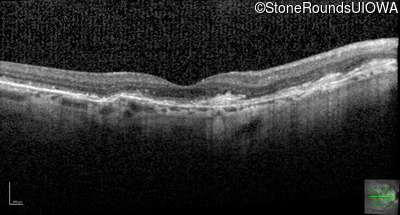

Optical Coherence Tomography - Left - 20/20 -2

Exemplar / OCT Stack

OCT Stack